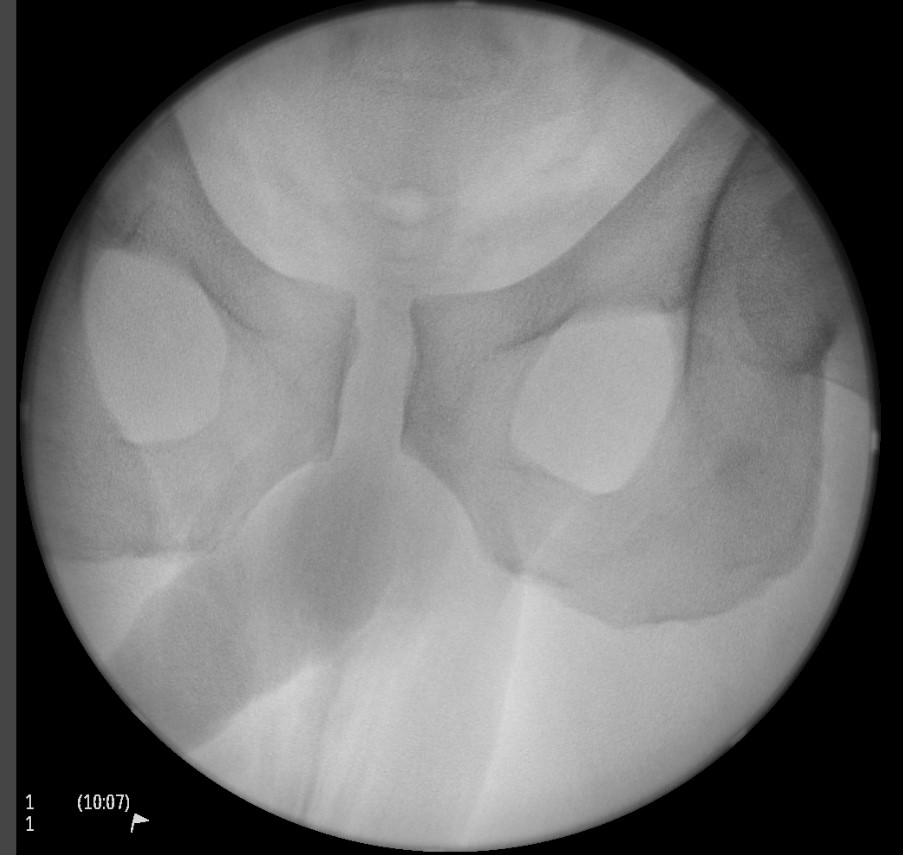

Radiolucent table with image intensifier

- 45o cephalad and caudal / inlet and outlet views

Guide wire insertion into body of S1

- anatomic safe zone

- between S1 foramen and superior ala on outlet view (outlet view)

- between neural canal and anterior body (inlet view)